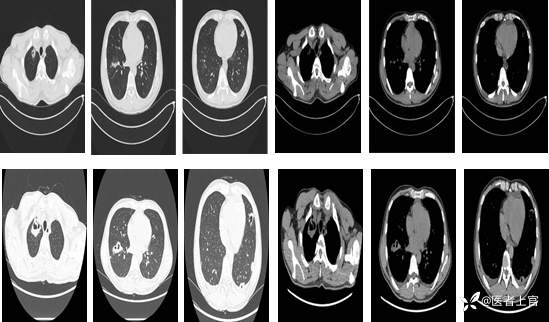

2023-4-16【胸部CT】两肺感染,考虑炎症,建议结合临床。心包少量积液。

2023-4-29【胸部增强CT】1.两肺多发肺脓疡,双侧少量胸腔积液。 2.心包少量积液。

2023-04-16上面一排, 2023-04-29下面一排